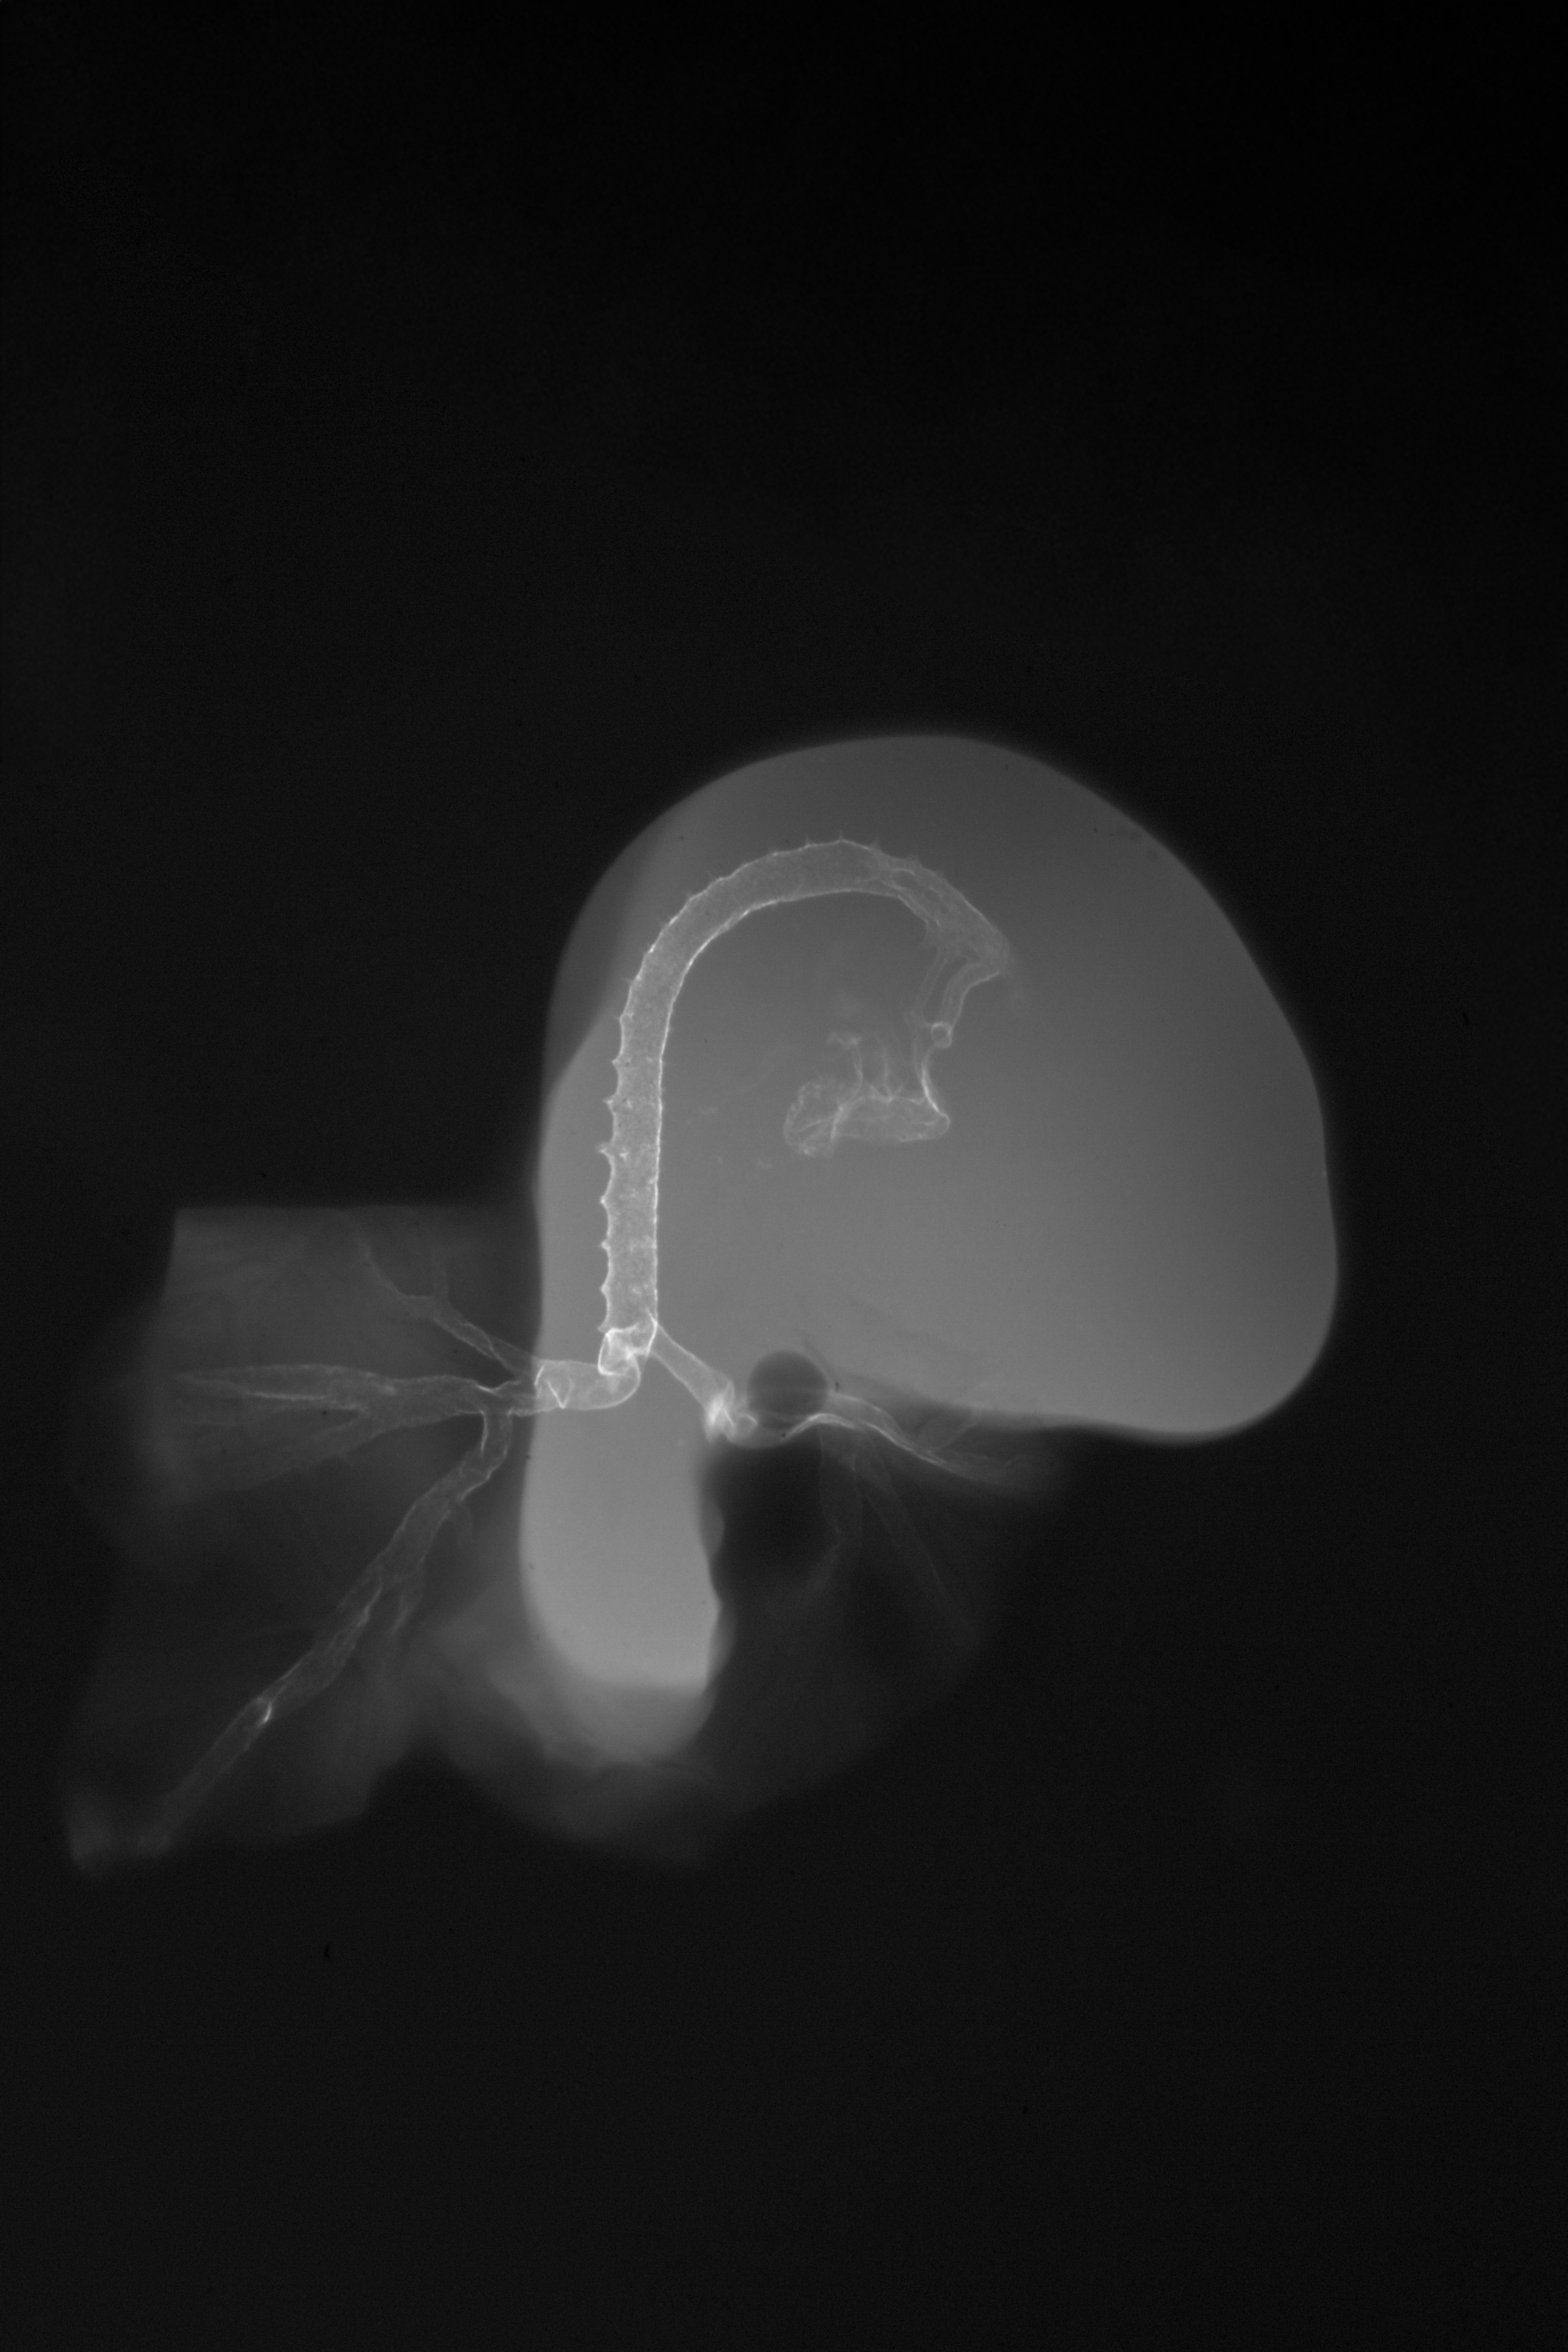

Chick Embryo Microangiography

Hamburger-Hamilton (HH) Stage 19 (approx. 3 - 3.5 days)

X-Ray Micrographs